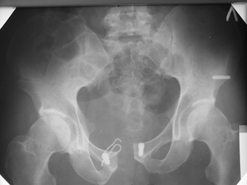

Диагноз : Сочетанная травма. ЗЧМТ. Перелом свода черепа. Ушиб головного мозга.Разрыв лонного и крестцово-подвздошного сочленений с нарушением целостности тазового кольца, с массивной забрюшинной гематомой и пропотеванием в брюшную полость. Перелом 10 ребра справа, осложненный гемопневмотораксом справа, правосторонней пневмонией на фоне ушиба правого легкого. Шок 3-4 ст. Больной поступил в отделение 07.03.2005г. в 16.00 в экстренном порядке через 30 минут после автодорожной травмы.Доставлен КСП. При поступлении состояние больного крайне тяжелое, явления травматического шока, А/Д-80/60 мм.рт. ст. ЧСС-120.В экстренном порядке поднят в операционную, интубирован, совместно с диагностическими мероприятиями лечение шока.При осмотре выявлены перелом 10 ребра справа, разрыв лонного и правого крестцово-подвздошного сочленений. Имеется линейный перелом теменной и височной костей слева с переходом на основание. Диагностическая лапароскопия 07.03.2005г. в 16.30-массивная забрюшинная гематома малого таза.Оставлена контрольная, дренажная трубка.Учитывая кровь в моче произведена цистография - данных за разрыв мочевого пузыря не найдено. Больной переведен в реанимационное отделение.За 08.03.2005г. из брюшной полости выделилось до 1500,0 мл, крови, часть крови реинфузирована. 08.03. в 06.30 наложен торокоцентез справа,удалено 100,0 мл. крови и 200,0 мл. воздуха .. Учитывая продолжающеееся кровотечение в брюшную полость из перелома костей таза, для исключения возможного разрыва внутренних органов 09.03.2005г. произведена Видеолапароскопия., на которой повреждения органов брюшной полости не выявлено.Одновременно произведен шов лонного сочленения проволокой и винтами, с одномоментным наложением стержневого аппарата на кости таза, с целью уменьшения кровотечения из разрывов тазовых сочленений, дренирование гематом. В последующем состояние больного оставалось тяжелым. 10.03.наложена нижняя трахеостома.Далее неоднократно производилась лечебно-диагностическая ФБС.С 10.03 выявлена правосторонняя плевропневмония. КТ головного мозга от 10.03-субарахноидальноекровоизлияние.Срединные структуры не смещены. КТ-контроль от 15.03-открытая моновентрикулярная гидроцефалия4 желудочка. Полисинусит. Постепенно состояние больного медленно прогрессировало к улучшению.С 24.03 переведен на самостоятельное дыхание, а 09.03 переведен в травматологическое отделение.Аппарат стержневой снят из-за перелома стержня (раскрутил больной самостоятельно).После госпитализации в наше отделение проведено дополнительное обследование Рентгекнография, КТ.Хотелось бы услышать Ваше мнение о дальнейшей тактике.-- С уважением, Leonid

Углядел билатеральное повреждение таза. Имеется вертикальная нестабильность со стороны перелома боковой массы крестца, ротационная с контрлатеральной стороны - чрезподвздошный разрыв кп сочленения. Разрыв лона, запирательные отверстия вроде целы.

DS. на сегодняшний день: Вертикальная двусторонняя нестабильная деформация таза, неправильно срастающийся перелом боковой массы крестца слева, срастающийся перелом крыла правой подвздошной кости, застарелый частичный разрыв правого кп сочленения, застарелый разрыв лонного сочленения.

План жизни - оперативное лечение. ЧКО таза (кольцевая опора), последовательная фиксация задних отделов с низведением перелома крестца, синтез лона пластинами, илиосакральное блокирование.

Следует заметить, что подобное привинчивание проволокой лонных костей редко приносит удовлетворение и то только при ротационно-нестабильных повреждениях от бовового сжатия без "ручки корзины". Разрушение заднего комплекса делает неэффективным любую фиксацию передних отделов. Надо обезательно хватать задние отделы.